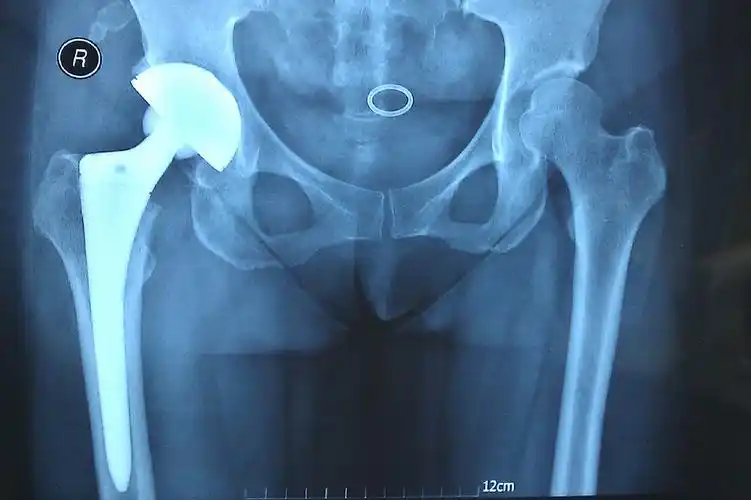

人工髋 关节置换 术后的x光片